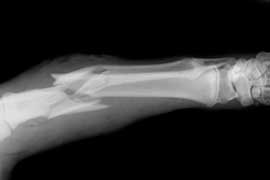

El efecto de la terapia con bisfosfonatos a largo plazo sobre la resistencia ósea trabecular y la densidad de microgrietas

Se halló reducción de la resistencia y un aumento de microgrietas en el hueso tratado con bifosfonatos. Bone Joint Res, 27 de octubre de 2017